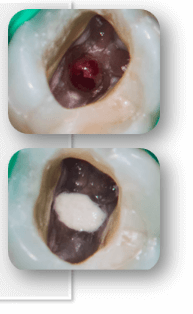

- Stop drilling immediately if you see unusual bleeding.

- Optional inspect visually using magnification (dental microscope or 3.5 X loupes).

- Dry the area gently with sterile cotton pellets to locate the perforation site.

Step 1: start quickly

Step 2 and Step 3

Step 2: clean the perforation site

Step 3: control bleeding